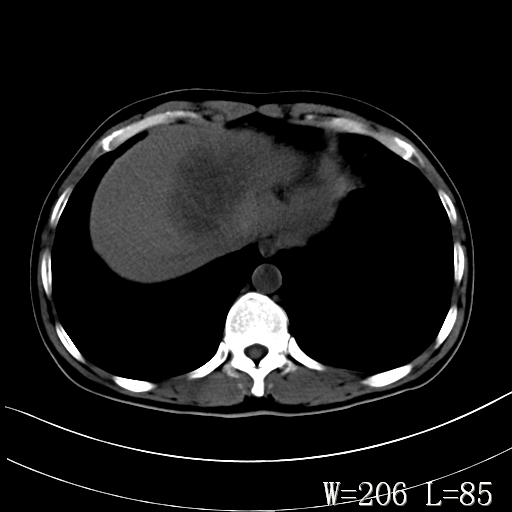

标题: CT27340:肝脏病变? [打印本页]

标题: CT27340:肝脏病变?

男,45岁,发热、乏力半月,午后为主。

对比剂快进快出,首先考虑肝左叶巨块型肝癌。

其次,感染性病变,如肝脓疡不排除。

肝脓肿可能。

蜂巢,肝脓肿

蜂巢状,支持!肝脓肿的诊断。